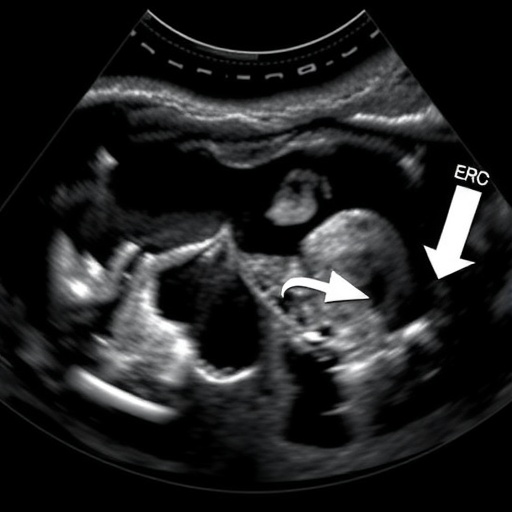

Utilizing UDFF, the researchers collected data from a diverse cohort of children, enabling a thorough analysis of the relationship between BMI and liver fat. By examining these variables collectively, the authors sought to unveil patterns previously overlooked in smaller studies. The research also underscores the importance of non-invasive techniques, such as ultrasound, which holds promise for widespread clinical application in evaluating children’s metabolic health without subjecting them to potential harms of invasive procedures.